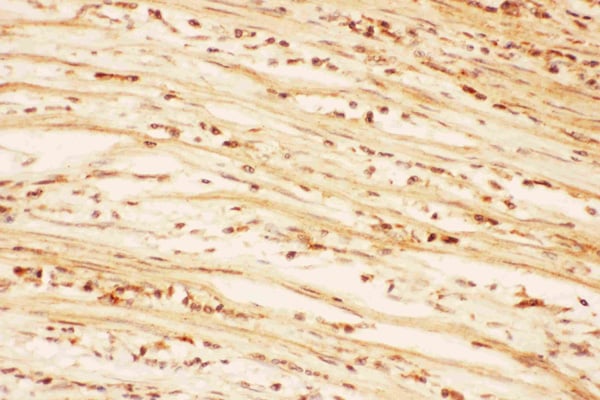

IHC (Immunohistochemistry)

(Anti-AKT2 Picoband antibody, AAA45720-1.JPGIHC(P): Human Intestinal Cancer Tissue)